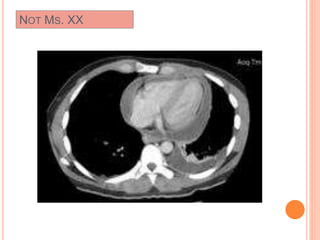

NOT MS. XX

CT scans

Mediastinal Window